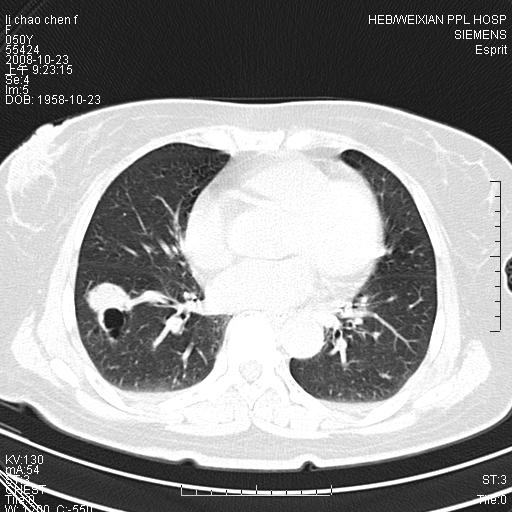

体检发现肺部肿块,现无不适。五年前曾有过哮喘病史。

先对现有的图象资料谈几点看法:病变位于右肺下叶前基底段,上部呈类圆形改变,分叶及毛刺征象不明显,下部呈不规则气腔改变,近肺门侧可见与一粗大血管相连,考虑为引流静脉影.其他肺叶相对正常所见.分析:该病灶良恶性均有可能.(现有资料来说).强化及穿刺活检有助鉴别.

考虑右肺下叶前基底段周围型肺癌可能性大。

右肺下叶前基底段占位性病变,不排除周围型肺癌可能,尽快手术为妙。

右肺下叶前基底段周围型肺癌可能性大。